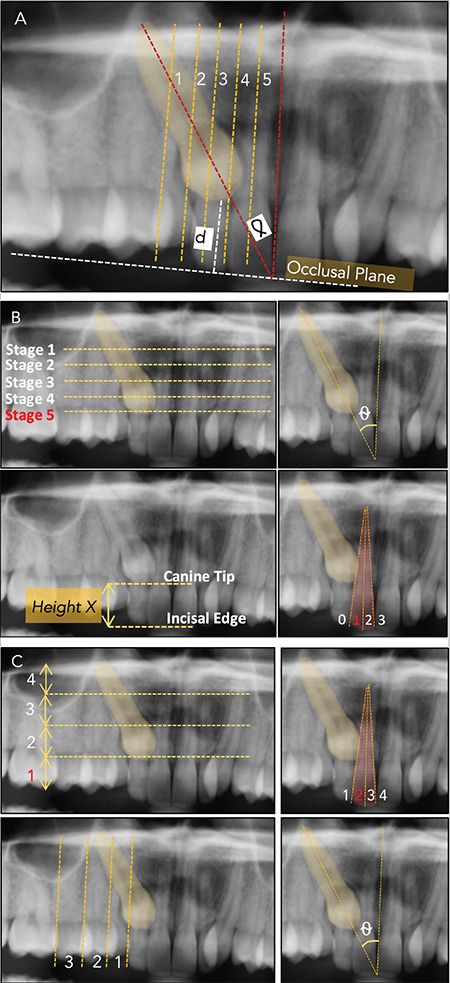

A thorough clinical and radiographical assessment of an impacted maxillary canine's location forms the basis for proper diagnosis and successful treatment outcomes. Implementing a correct biomechanical approach for directing force application primarily relies on its precise localization. Poor biomechanical planning can resorb the roots of adjacent teeth and result in poor periodontal outcomes of the canine that has been disimpacted. Furthermore, treatment success and time strongly rely on an accurate assessment of the severity of impaction, which depends on its 3D spatial location. The evolution of cone-beam computed tomography (CBCT) radiographs provides more detailed information regarding the location of the impacted canines. In addition, the literature has shown that CBCT imaging has enhanced the quality of diagnosis and treatment planning by obtaining a more precise localization of impacted canines. This review article highlights current evidence regarding comprehensive evaluation of three-dimensional orientations of impacted canines on CBCT images for precise diagnosis and treatment planning.